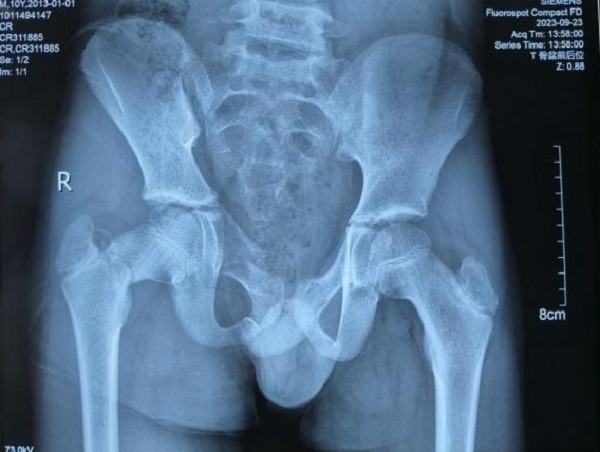

10岁的小陈玩耍时不慎从高处坠落,导致全身多处疼痛、流血2小时,入院呼吸急促,发现右下肢短缩,诊断为骨盆骨折(C1-2)、右股骨颈骨折、右侧气胸、右肺挫伤、右侧桡骨远端骨骺损伤、右侧尺骨远端骨折、右下颌皮肤裂伤、下颌骨骨折,在严密监测生命体征的同时,立即行右侧股骨髁上骨牵引、右侧胸腔闭式引流、伤口清创缝合等对症处理。

小陈骨盆骨折Tile分型为C1-2骶髂关节骨折并脱位;Torode-Zieg儿童骨盆骨折分型为4b型,右侧骨盆整体移位,同时合并右侧股骨颈骨折,需手术复位固定。潘建宏主任考虑到患儿年龄小,手术难度大,科室多次讨论后,计划采取闭合复位微创固定,在全麻下进行了“骨盆骨折及右侧股骨颈骨折闭合复位内固定术”,闭合复位成功后,骨盆后环经皮空心螺钉固定、骨盆前环使用外固定固定,股骨颈骨折使用经皮空心钉及克什针固定,术后使用髋人字石膏固定制动,微创手术顺利完成,术后,患者恢复顺利,现已出院。